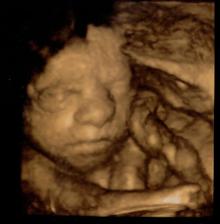

Dne 11.3.2009 nastal den D a já našla na těhotenském testu znovu // čárky. S manželem jsme si jisti, že tentokrát to dopadne dobře a my se konečně dočkáme našeho vytouženého zlatíčka.

Broučka jsme se opravdu dočkali. Dne 25.10.2009 v 19.24 hod. přišel předčasně na svět (35 tt). I když se narodil dříve, je to čiperka a má se čile k světu. Jmenuje se Matyášek a je to naše velké zlatíčko.